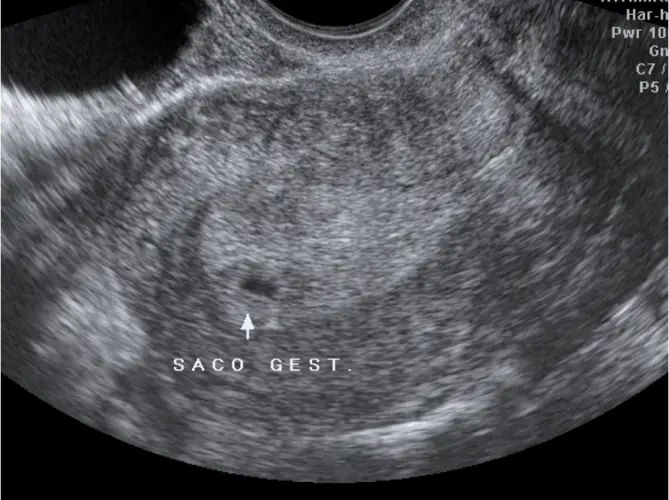

Ainda é muito cedo para realizar ultrassonografia, pois o embrião é extremamente pequeno e pode não ser visualizado. A primeira ultrassonografia geralmente é realizada entre a 6ª e 8ª semana, quando já é possível observar o saco gestacional e, com sorte, os primeiros batimentos cardíacos.